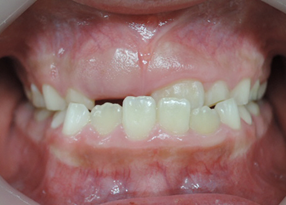

初診時より1年6カ月後 終了時(8歳8か月)

終了時より2年2カ月後(10歳11か月)

初診時より2年2カ月後

一口メモ 上顎左右の切歯が逆に咬んでいる以外はほぼ問題のない咬み合わせになりました。早期に治療を開始していなければ大変、治療に苦労する症例となっているはずでしたが改善する事が出来ました。